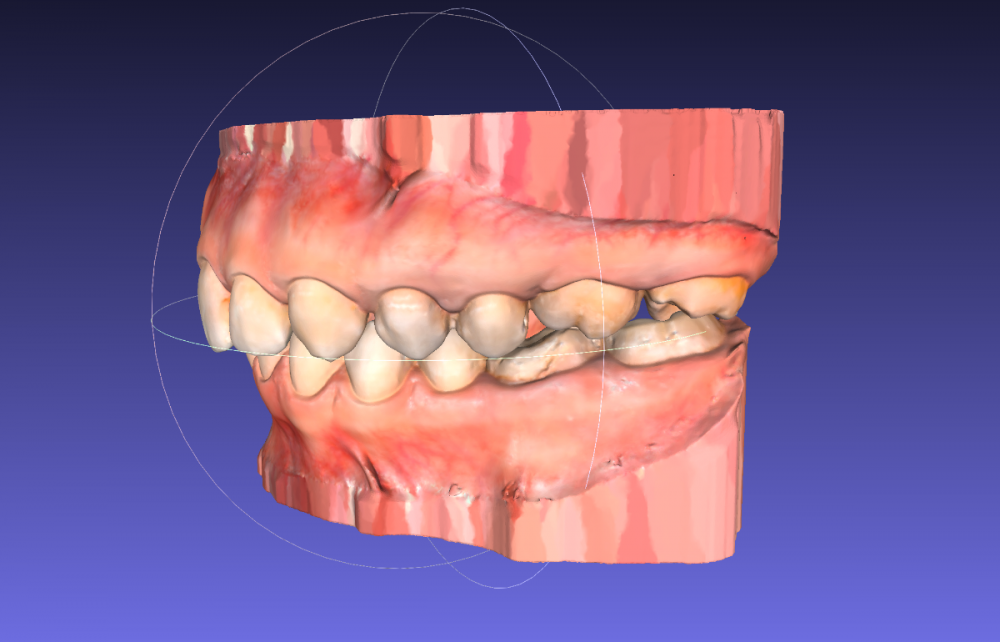

Сейчас я обратилась к ортодонтам с целью выровнять только нижний зубной ряд (искривлен из за воздействия 8ок), с последующей установкой импланта (46 зуб). Нижние восьмерки удалены.

26 отсутствует, 27 стоит на месте 26, 28 стоит на месте 27

11 сломан в корне, держится на штифте + пломба соединяющая его с соседними зубами.

Лечение планирую исключительно на элайнерах.